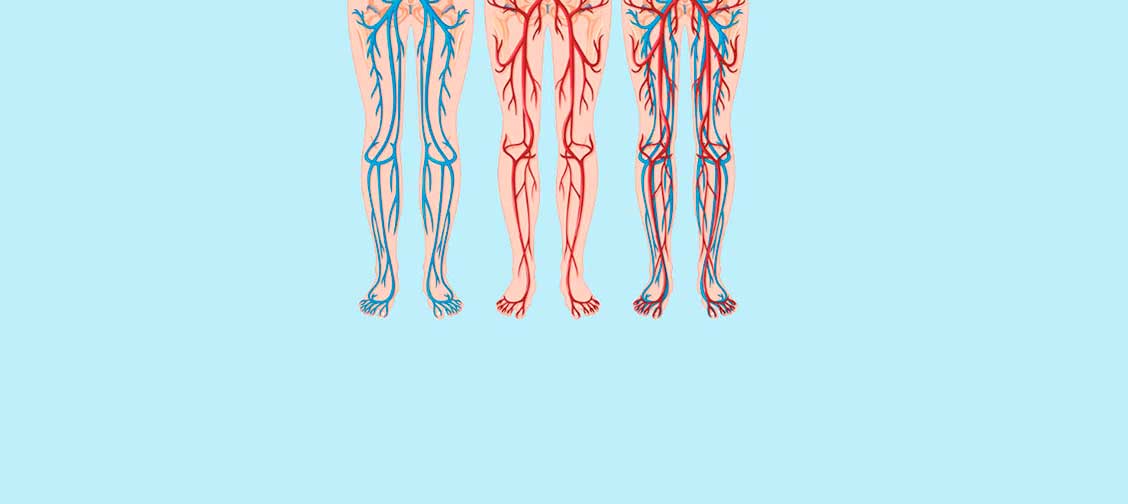

Organ dalaman pesakit diabetes kelihatan seperti ceri

gula-gula. Hati, perut, buah pinggang, jantung, dan yang

paling penting saluran darah...

Organ dalaman pesakit diabetes kelihatan seperti ceri

gula-gula. Hati, perut, buah pinggang, jantung, dan yang

paling penting saluran darah...

Masalah pembuluh darah dan organ dalaman!

Bayangkan ceri atau raspberi gula-gula. Perkara yang sama berlaku pada semua saluran darah anda jika anda menghidap diabetes. Dinding saluran darah menjadi tepu dengan gula dan rapuh. Akibatnya, saluran darah kehilangan kemampuan untuk menyempit dan mengembang. Saluran darah yang lebih kecil mati pertama, segera diikuti oleh saluran yang sederhana dan besar. Saluran darah memberi makan kepada organ dalaman. Kemerosotan bekalan darah membawa kepada perkembangan penyakit kronik.